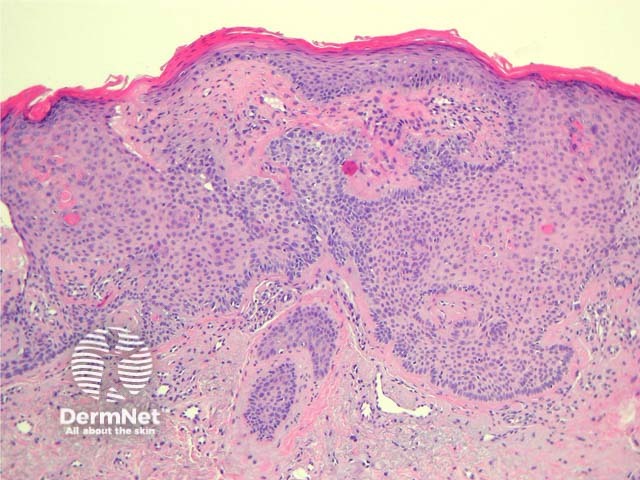

In tumour of the follicular infundibulum, sections show an acanthoma composed of pale pink cells and sometimes clear cells. The tumour forms anastomosing narrow strands that run parallel to the epidermis. These strands have peripheral palisading of basaloid cells (figures 1, 2).

Figure 2